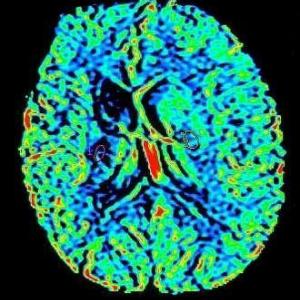

Die Kernspintomographie liefert detailgenaue Schnittbildaufnahmen des menschlichen Körpers ohne Röntgenstrahlen – und das sogar von Blutgefäßen. Bei der MRT werden Sie in einem starken Magnetfeld untersucht. Ähnlich wie bei einem Radio werden UKW-Wellen verwendet. Um dünne Schichtaufnahmen zu erzeugen, benötigen wir zusätzlich schwach wechselnde Magnetfelder, wodurch ein lautes Klopfgeräusch entsteht. Die Signale werden dann von einem sehr leistungsfähigen Computersystem zu Schichtaufnahmen in verschiedenen Ebenen umgewandelt. Die Untersuchung dauert je nach Fragestellung 7 bis 35 Minuten. Während der Messzeit sollten Sie ruhig und entspannt liegen, denn jede Bewegung verursacht Bildstörungen und verlängert die Prozedur.